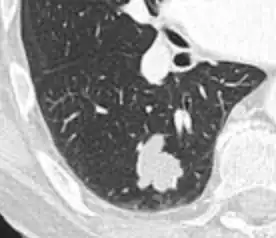

Round well-delineated solid lung nodule with smooth border.[9]

Lobulated nodule.[9]

Spiculated lung nodule.[9]